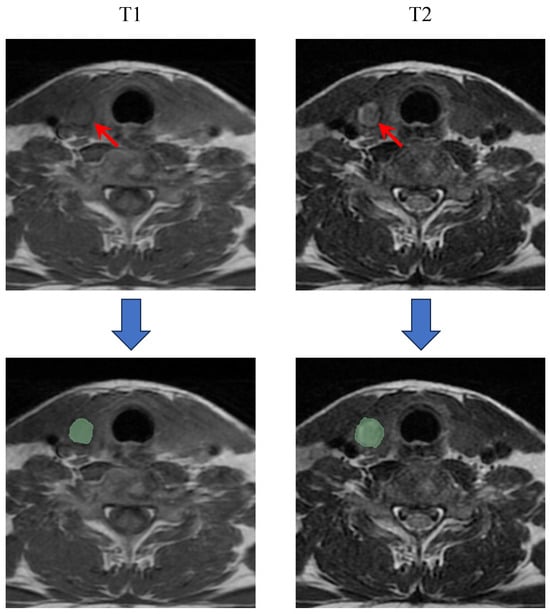

2.3. ROI Segmentation

MRI images from all patients were imported into 3D-Slicer software (version 5.2.2; http://www.slicer.org) for precise ROI segmentation (Figure 2). Following the previous research, for PTC patients with multiple lesions, the largest one was selected for analysis [9]. Initially, two radiologists determined the largest cross-sectional area of the primary tumor on T1WI and T2WI images in consensus. The ROI on the largest cross-sectional images was meticulously outlined by a junior radiologist (Observer 1, with 5 years of experience), carefully avoiding surrounding normal thyroid tissue. To ensure repeatability and consistency in the ROI delineation, intra-observer and inter-observer consistency checks were performed. Two weeks after the initial delineation, 30 cases were randomly selected for re-segmentation by Observer 1, and another experienced radiologist (Observer 2, with 10 years of experience) segmented the same 30 cases. Intra-observer and inter-observer consistency between segmentations was assessed by calculating the class correlation coefficient (CCC). A CCC greater than 0.75 indicates a high level of consistency in the ROI segmentation process. Figure 2 shows representative ROI delineations on T1WI and T2WI images.

Figure 2. Segmentation of the ROI in axial T1 and T2 images. The red arrows in the MRI images indicate the location of the primary lesion.